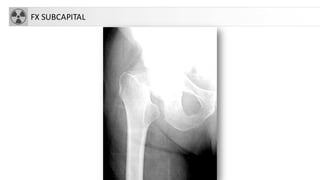

FX SUBCAPITAL

CLASIFICACIÓN

• Fracturascapitales: raras, asociadas a

luxación

• Fracturascervicales (intraarticulares)

1. subcapitales.

2. transcervicales

3. basicervicales

• 4. Fracturastrocantereas:

• cervicotrocantereas

• pertrocantereas(+frecuente)

• 5. Fracturassubtrocantereas

• Aisladas de trocanter mayor

• Aisladas de trocánter menor

FX EXTREMO PROXIMAL DE FÉMUR

• 33.000 casos nuevos/año

(España)

• Alta morbimortalidad (20-

30% mueren antes de 6

meses)

• Asociadas a envejecimiento.